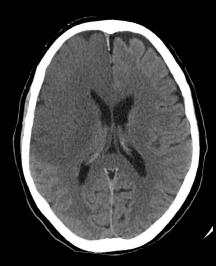

The primary treatment for nonhemorrhagic strokes is the administration of thrombolytics (e.g. tissue plasminogen activator, t-PA) prior to the development of ischemic necrosis. Since thrombolytics would exacerbate hemorrhagic bleeds, the distinction between hemorrhagic and nonhemorrhagic strokes is critical. Fortunately, as you can see, the distinction is quite apparent on a non-contrast CT scan.

When examining these CTs, remember that collections of blood will be radiodense. Initially infarcted brain will show minimal changes on a CT, but after a few days, there is marked effacement of the normal architecture.

Can you distinguish between these CTs and assign them each to one of the aforementioned categories?